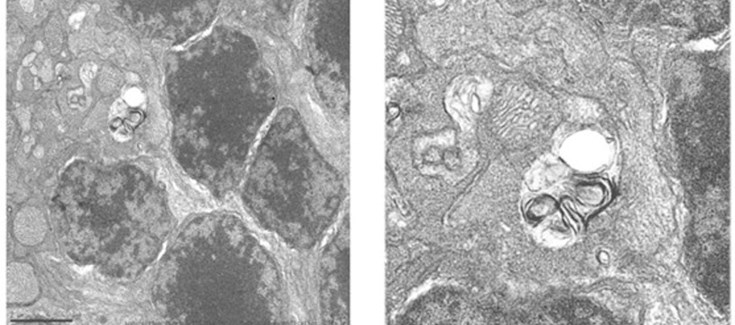

“Hemos encontrado que estos ratones presentan una inflamación crónica en la retina, con una importante activación de la microglía que se ve atenuada mediante la activación del flujo autofágico a los 6 meses de edad”, explica Ángela Martínez Valverde, coautora del trabajo e investigadora del IIBM y el CIBERDEM.

“Sin embargo, en ratones envejecidos de 12 meses de edad se produce un bloqueo de la autofagia que resulta en un aumento del número de autofagosomas en la retina. Este hecho, unido a otros procesos como la activación persistente de la microglía y del sistema inflamosoma, contribuye de manera importante a las alteraciones estructurales de la retina y a la pérdida de la función visual de los ratones deficientes en Igf1 durante el envejecimiento”, añade Isabel Varela-Nieto, también coautora y jefa de grupo de la U761 CIBERER.